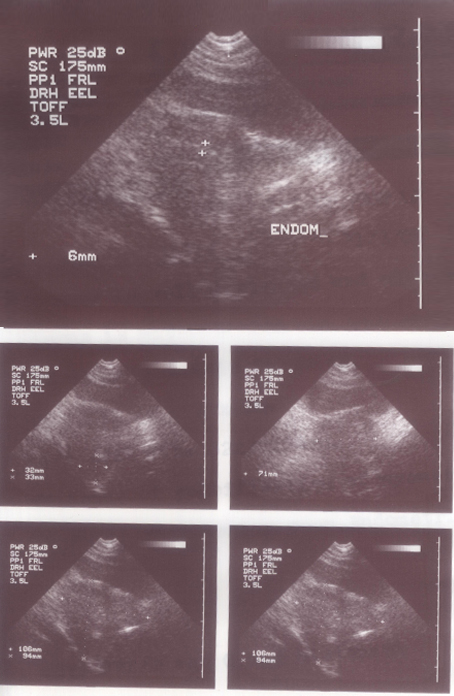

Before the treatment:

Her Ultrasound was repeated in November 2008, which showed a decrease in the size of the fibroid, but the endometrial thickness was a matter of concern. With continued treatment latest ultrasound, done in March 2009, showed a marked reduction in the size of the fibroids and also the endometrial thickness came down to 6 mm.